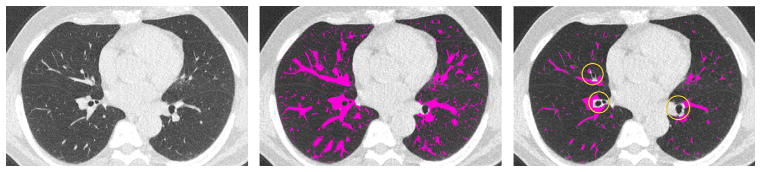

Overall, the most difficult categories turn out to be Mucus-filled bronchi (7th) and Nodules (9th). Several methods filtered the images to remove known non-vessel structures such as fissures, airway walls, and nodules. Methods which explicitly exclude nodules have less false positives on nodules, as can be seen in Fig. 11(f). Similarly, airway wall exclusion also reduces false positives, as shown in Fig. 12. The Vessel-in-Consolidation/Consolidation (8th) category is another difficult category; none of the methods was very successful in this task.

Fig. 12.

Effect of explicit exclusion of airway walls on vessel segmentation of scan 04 (left to right): original, with no airway wall removal (method K), and airway wall excluded (method O) where the bright circles indicate airway walls which were removed explicitly. Middle image shows oversegmentation, not severely penalized because our choice of evaluation method. Refer to text of Section 6.2 for details.

Most intensity threshold-based methods include high-density structures in the lung which are not vessels. For this reason, many submissions include postprocessing steps, which explicitly excludes known structures such as airway walls, nodules, and lobar fissures. However, the postprocessing steps do not always ensure better performance. In many cases postprocessing does not catch all false positives and could be improved.